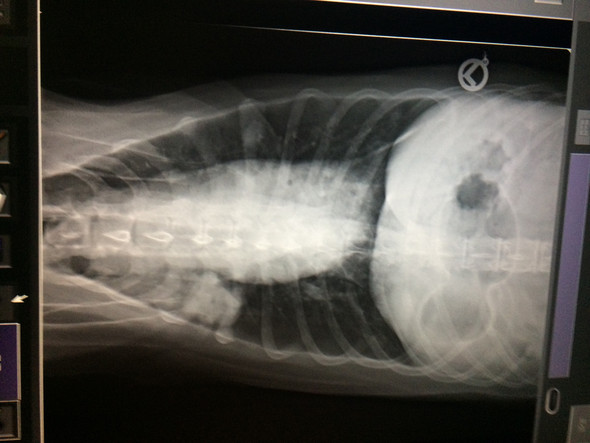

Lungen CT und Volumentomografie der Lunge beim Hund beim unklaren From www.tierarzt-sommer.de

Lungen CT und Volumentomografie der Lunge beim Hund beim unklaren